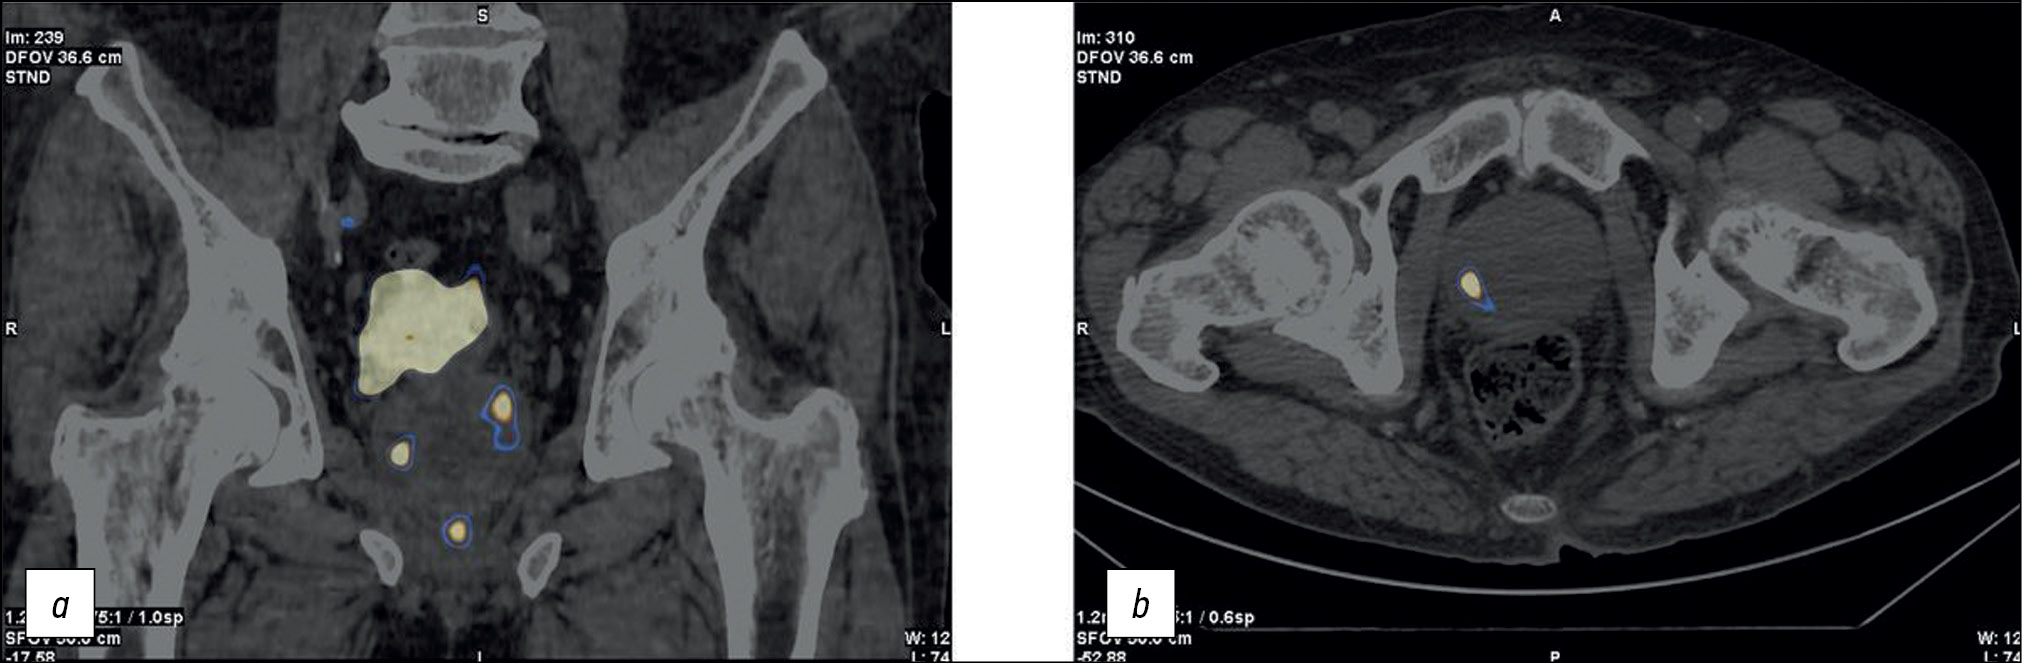

Patient K., 73 years old, was admitted with diffuse prostatic hyperplasia, urinary retention, an epicystostomy, and a 12.7-ng/mL PSA. A multisite biopsy performed under US guide revealed no evidence of malignant development. SPECT/CT data with 99mTc-HYNIC-PSMA are shown in Figure 4. SPECT/CT revealed a 14-mm3 site of RP accumulation in the prostate tissue. A CT-guided targeted biopsy was performed using pararectal access. A morphological diagnosis was adenocarcinoma, Gleason 6 (3 + 3).

Fig. 4. Patient K., 73 years old, SPECT /CT with 99mTc-HYNIC-PSMA, (a) frontal and (b) axial sections: Sites of radiopharmaceutical accumulation in the anterior part of the transition zone in the apex of the right lobe, posterolateral part of the peripheral zone at the level of the base of the left lobe, and posterolateral part of the peripheral zones at the level of the base and middle third of the left lobe of the prostate gland; physiological accumulation of radiopharmaceuticals in the bladder.

On November 28, 2020, CT-guided focal implantation of 125I sources was performed pararectally. Transurethral resection of the intravesical component was performed, and the epicystostomy was removed. The follow-up examination (November 28, 2022) showed a PSA level of 0.13 ng/mL, spontaneous urination, and 15-cm3 residual urine.

In this case, problems were as follows: inability to identify the cause of elevated PSA, a “large” volume of the prostate gland, and epicystostomy. Considering data on RP accumulation patterns and biopsy results, we were unable to successfully solve these problems and perform successful focal brachytherapy using a hybrid diagnostic use of RP CT-guided biopsy.